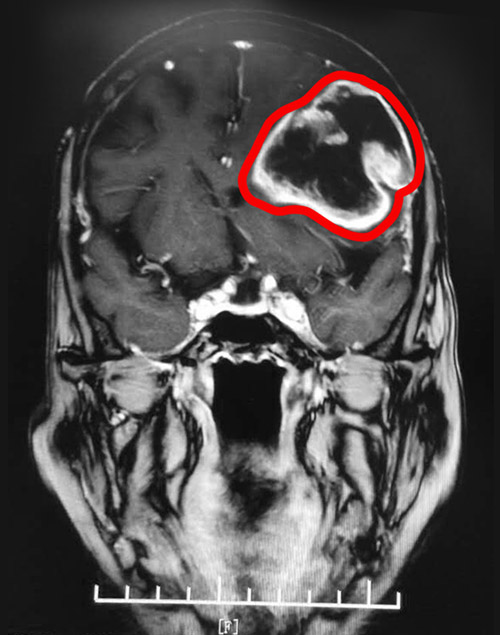

▲MRI影像显示,患者左脑有一个大小约5.8*5.6cm的肿瘤

不查不知道,一查吓一跳!MRI影像显示,患者左侧额颞顶叶存在大面积不规则形的低密度影,几乎占据了左侧大脑的一半位置。脑中线已发生偏移,病灶周围明显水肿。至此,一个大小约5.8*5.6cm的脑部肿瘤,终于现形了。